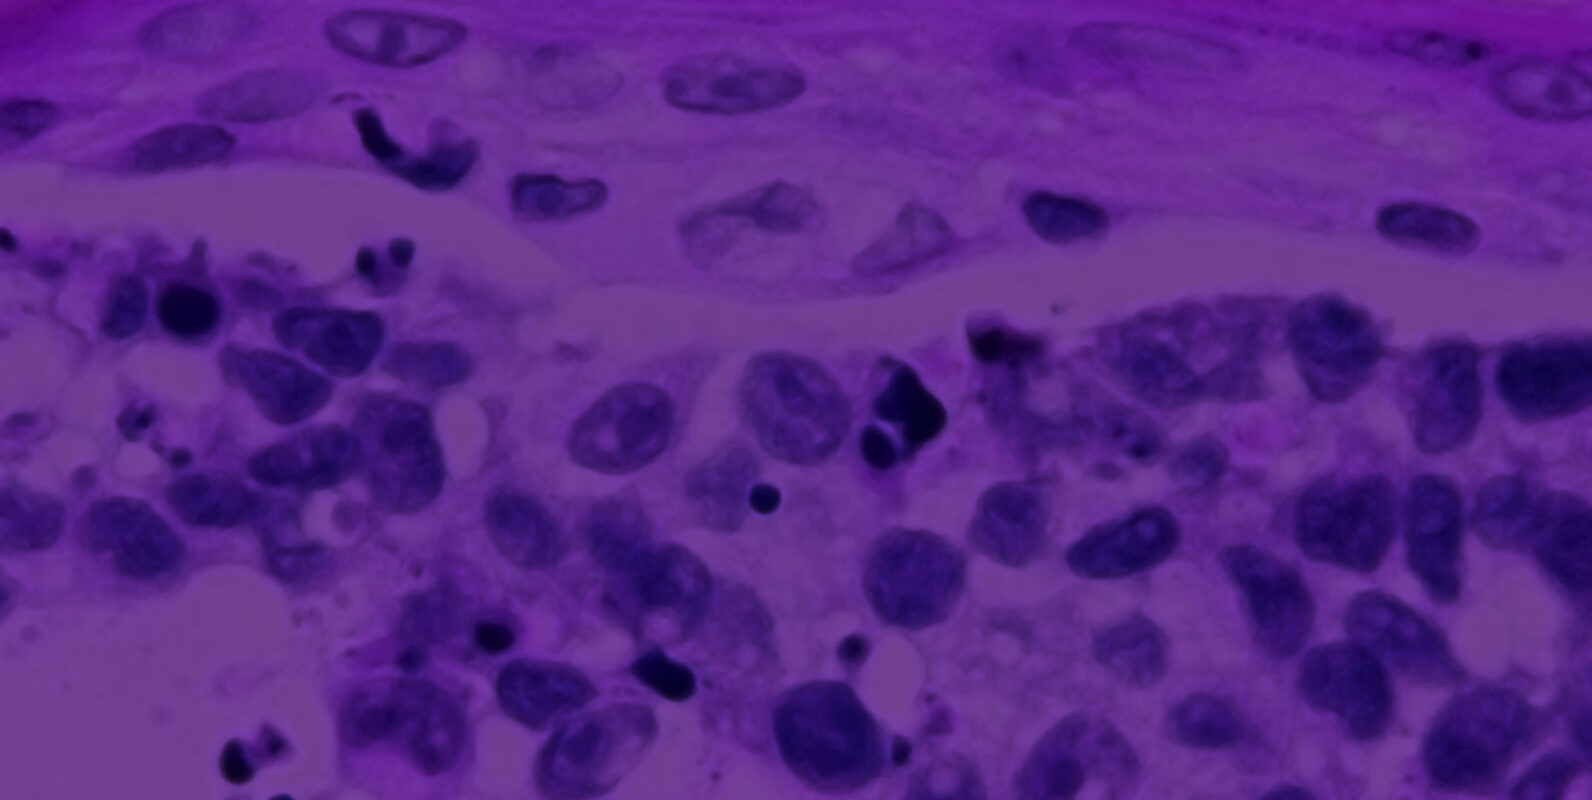

To conduct this study, OSUCCC – James researchers developed genetically engineered models that would allow them to activate one of nine different NRAS-mutant variations in melanocytes, the pigment cells that form melanoma.

“Amazingly, when we activated these gene mutations only those found in the human disease caused melanoma to develop,” said Burd. “Some mutants never led to melanoma, yet we know that they cause leukemia. This finding shows that selection of NRAS mutations is specific to each tumor type and occurs during cancer initiation, rather than in response to a specific mutagenic event like sun exposure.”